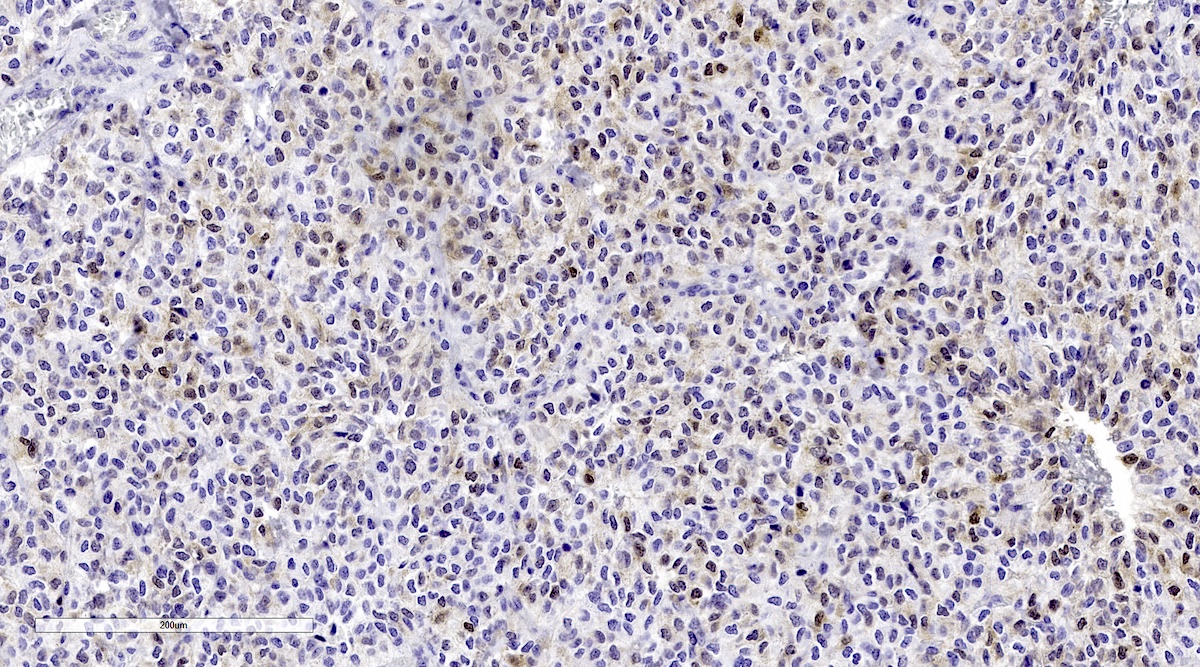

Microscopic (histologic) images

Contributed by Luvy Delfin, M.D. and Sylvia L. Asa, M.D., Ph.D.

Positive stains

- INSM1 (diffuse nuclear) (Am J Surg Pathol 2018;42:665)

- Chromogranin A (can be only focal or perinuclear dot-like golgi pattern)

- Synaptophysin (Histol Histopathol 1993;8:429)

- CD56 (Endocr Pathol 2002;13:149)

- S100 may be diffusely positive (J BUON 2018;23:1540)

- GATA3 (diffuse nuclear) (Hum Pathol 2020;103:72, Am J Surg Pathol 2014;38:13, J Clin Med 2018;7:280)

- Tyrosine hydroxylase (critical enzyme required for catecholamine synthesis; usually diffuse and strong in sympathetic paragangliomas, may be weak or focal in parasympathetic tumors) (Hum Pathol 2020;103:72)

- Dopamine beta hydroxylase and phenylethanolamine N methyltransferase (PNMT) (epinephrine producing tumors) (see Diagram below) (Neuroendocrinology 2015;101:289, J Clin Med 2018;7:280)

- Sustentacular cells: S100, GFAP and SOX10 (Hum Pathol 2020;103:72)

Contributed by Luvy Delfin, M.D. and Sylvia L. Asa, M.D., Ph.D.